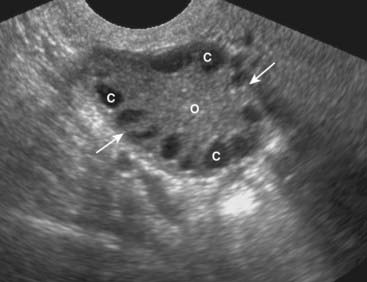

Figure 19-20 Polycystic ovarian disease.

Polycystic ovarian disease is an endocrine abnormality that allows for numerous ovarian follicles (>12 per ovary) to develop in various stages of hormonal growth and atresia. This ovary (O) is enlarged (solid white arrows) and contains multiple peripheral cysts, some of which are labeled (C). When associated with oligomenorrhea, hirsutism, and obesity, polycystic ovarian disease is called Stein-Leventhal syndrome.